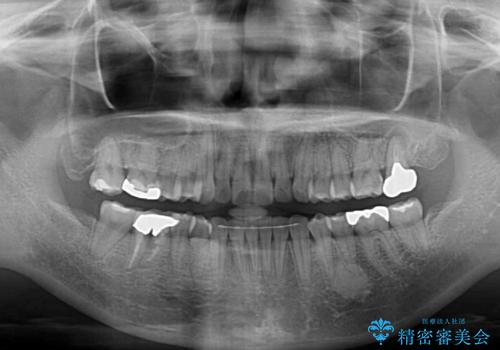

前歯のデコボコとクロスバイト インビザラインによる矯正治療

- 上下のクロスバイトと前歯のデコボコを気にして来院された患者様です。

骨格的に下顎がやや前方にあり、奥歯にクラウンが装着されているため、矯正治療後半の不安定な咬み合わせを避けるのであればワイヤー矯正がおすすめとなりますが、希望によりインビザラインにて治療を行うこととしました。

インビザラインを用い、IPR(歯と歯の間を削る)と歯列全体を拡大させることで、歯並びを整えていくこととしました。

懸念されたとおり、右下のクラウン部分が全く咬み合わず、仕上げの段階で治療期間が長くなりました。